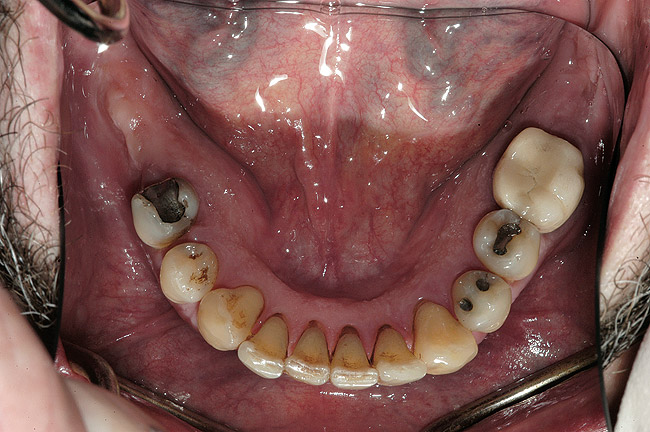

Examinarea a evidenţiat adâncimi de sondare generalizate cuprinse între 5-9mm, cu sângerare generalizată şi locaţii cu supuraţie. Combinaţia recesiunii cu adâncimile de sondare a generat o pierdere de ataşament generalizată cu valori între 8-12mm. Radiografiile au evidenţiat pierdere osoasă orizontală severă, defecte osoase verticale multiple şi aspectul unei posibile comunicări parodontale apicale. Aproximativ jumătate dintre dinţi prezentau mobilitate de clasa I, cu dinţii restanţi având o mobilitate de clasa a 2-a şi a 3-a. Toţi molarii manifestau cel puţin o invazie de furcaţie de gradul 1, cu multiple implicări de gradul 2 şi 3. Diagnosticul s-a stabilit a fi AAP tip IV, parodontită avansată.

La examinarea clinică, o serie de dinţi prezentau restaurări directe mici acceptabile. Dinţii de la 1.7. la 1.4., de la 1.2. la 2.6., 3.6. şi 4.5. prezentau fie restaurări directe voluminoase, fie coroane cu acoperire totală, cu un grad ridicat de compromitere structurală. Nu s-au identificat leziuni carioase active. Implicarea pulpară era vizibilă la nivelul molarului 3.6.

La examinare s-au obiectivat: dinamică labială maxilară crescută, cu afişarea în repaus a 3-4mm din incisivi. La zâmbetul total, marginile gingivale libere nu erau vizibile, datorită recesiunii, dar 2-4mm din structura radiculară era vizibilă dincolo de joncţiunea smalţ-cement (CEJ) la toţi dinţii superiori. Festonul ţesutului moale era apropiat de normal, însă părea neatractiv datorită gradului mare de recesie şi a pierderii papilei. În regiunea frontală inferioară s-a remarcat asimetria orizontală (fig. 2).

Obiective terapeutice

Consideraţiile privind managementul riscului şi planul de tratament au fost elaborate utilizându-se o abordare sistematică. Tratamentul ar fi redus riscul biomecanic prin eliminarea dinţilor compromişi structural (fig. 3,4), cu diminuarea concomitentă a riscului funcţional prin crearea unei ocluzii în armonie cu articulaţiile. În plus, tratamentul ar fi redus riscul parodontal prin îndepărtarea dinţilor irecuperabili, cu implicare parodontală, (fig. 5) şi ar fi îmbunătăţit estetica prin ridicarea cu 3mm a planului ocluzal pentru a minimiza expunerea gingivală şi a rădăcinilor.5-8